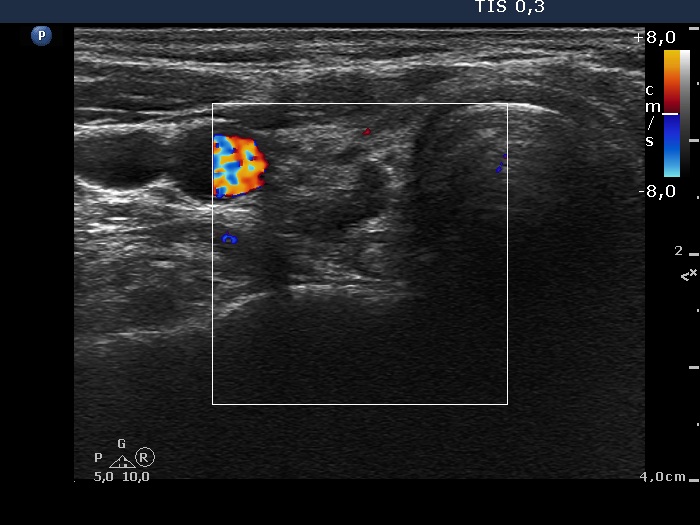

Follow-up examination 2 years later (ultrasonographic picture 3)

Right lobe, transverse scan, color Doppler mode. The vascularization is decreased.